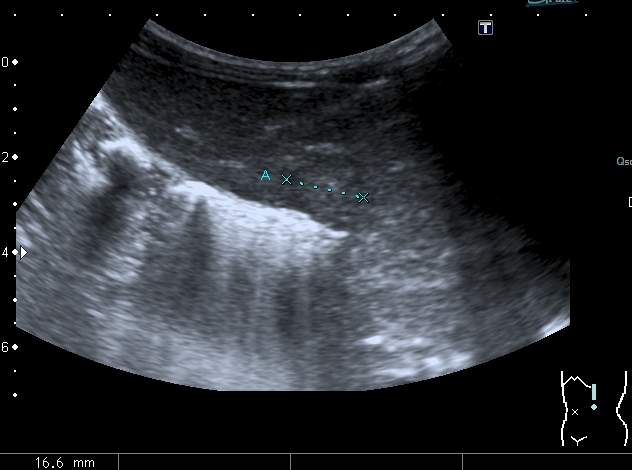

Правый надпочечник представлен округлым гиперэхогенным тканевым образованием с участками кальцификации, гиповаскулярным по отношению к ткани печени и почки